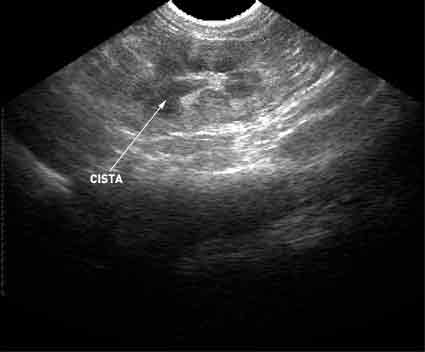

PKD diagnosticiramo z ultrazvočno preiskavo ledvic. To je neinvazivna in neboleča diagnostična metoda, ki omogoča ugotavljanje prisotnosti cist v ledvicah že zelo zgodaj. Preiskavo lahko naredimo že pri 8 do 10 tednov starih mucah, ki jih pred samim pregledom na trebuhu postrižemo; preiskavo pa izkušen veterinar s kvalitetnim ultrazvočnim aparatom opravi v nekaj minutah.

Ultrazvočni posnetek ledvičnih cist pri mački: